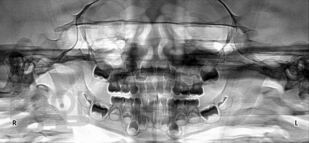

Лечение осложнений кариеса временных зубов у детей

Представлена анатомия полости рта у детей, приведены методологические подходы и современные методы лечения осложнений кариеса временных зубов с учетом общего состояния организма, возраста, психоэмоционального статуса ребенка, степени формирования и рассасывания корней, состояния периапикальных тканей. Предложен и апробирован уточненный протокол ведения детей, страдающих пульпитом и периодонтитом, который позволяет избежать существенных недостатков на диагностическом и клиническом этапах. Разработана количественная оценка качества эндодонтического лечения временных зубов, которая определяет пределы терапевтического вмешательства и тактику врача-стоматолога. Предложен механизм снижения врачебных ошибок и неблагоприятных исходов. В приложениях даны СанПин 2.1.3.2630-10 «Санитарно-эпидемиологические требования к организациям, осуществляющим медицинскую деятельность» (раздел «Стоматология»), а также приказы МЗ РФ № 210н, № 415н, регламентирующие вопросы организации стоматологической помощи детскому населению.